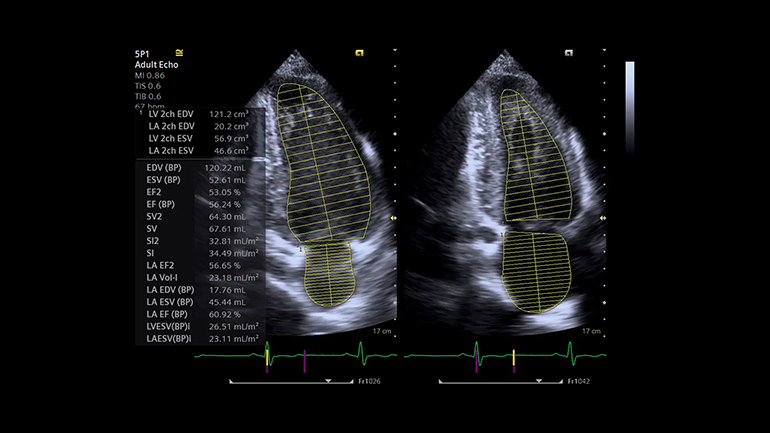

Технология выполнения измерений левых отделов сердца (eSie Left Heart). Пакет измерений левых отделов сердца eSie Left Heart — это надежный инструмент, который повышает надежность и оптимизирует рабочий процесс благодаря автоматическому определению границ левого желудочка и левого предсердия и выполнению измерений при стандартных трансторакальных исследованиях у взрослых пациентов.

Технология выполнения измерений левых отделов сердца (eSie Left Heart). Пакет измерений левых отделов сердца eSie Left Heart — это надежный инструмент, который повышает надежность и оптимизирует рабочий процесс благодаря автоматическому определению границ левого желудочка и левого предсердия и выполнению измерений при стандартных трансторакальных исследованиях у взрослых пациентов. Технология автоматического исследования фолликулов (syngo ® Auto Follicle). В технологии syngo ® Auto Follicle реализован автоматический метод измерений, обеспечивающий быструю и точную оценку фолликулов. Автоматическое выполнение измерений и запись результатов помогают сократить продолжительность исследования.